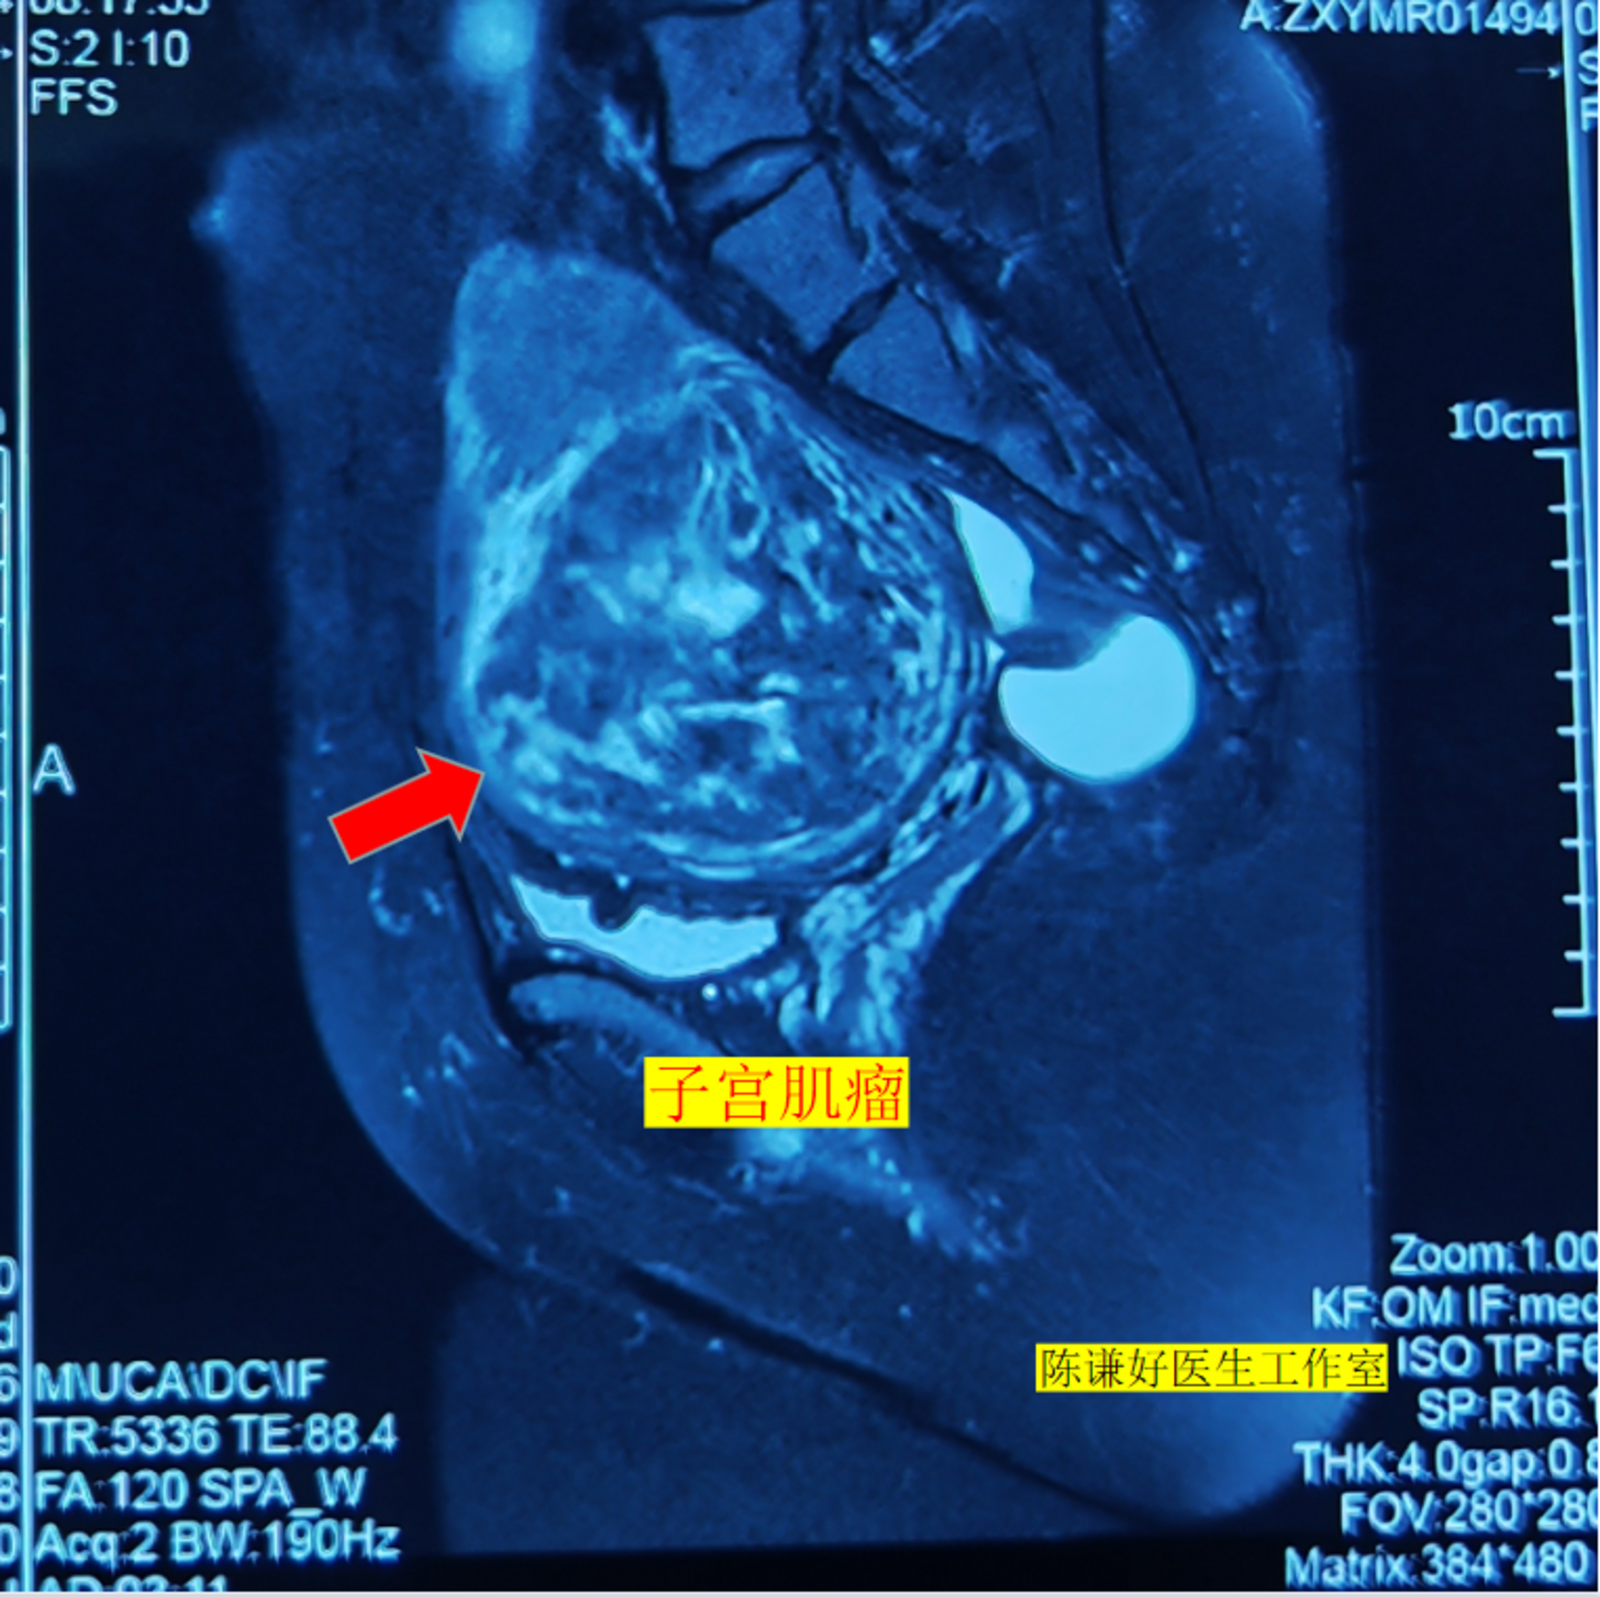

9.5厘米子宫肌瘤海扶刀治疗病例

患者在2018年发现子宫肌瘤,当时肌瘤有6cm,没有及时进一步治疗,之后肌瘤逐渐增大,现在肌瘤增大到9.5cm,同时伴有月经量增多,严重贫血。

患者不愿意选择传统手术,在了解到海扶刀可以无创的治疗子宫肌瘤后,专门从天津至我们中心进行治疗,不到40分钟肌瘤就完全消融,患者今天复查显示肌瘤消融满意,病人今天下午就正常回家了。